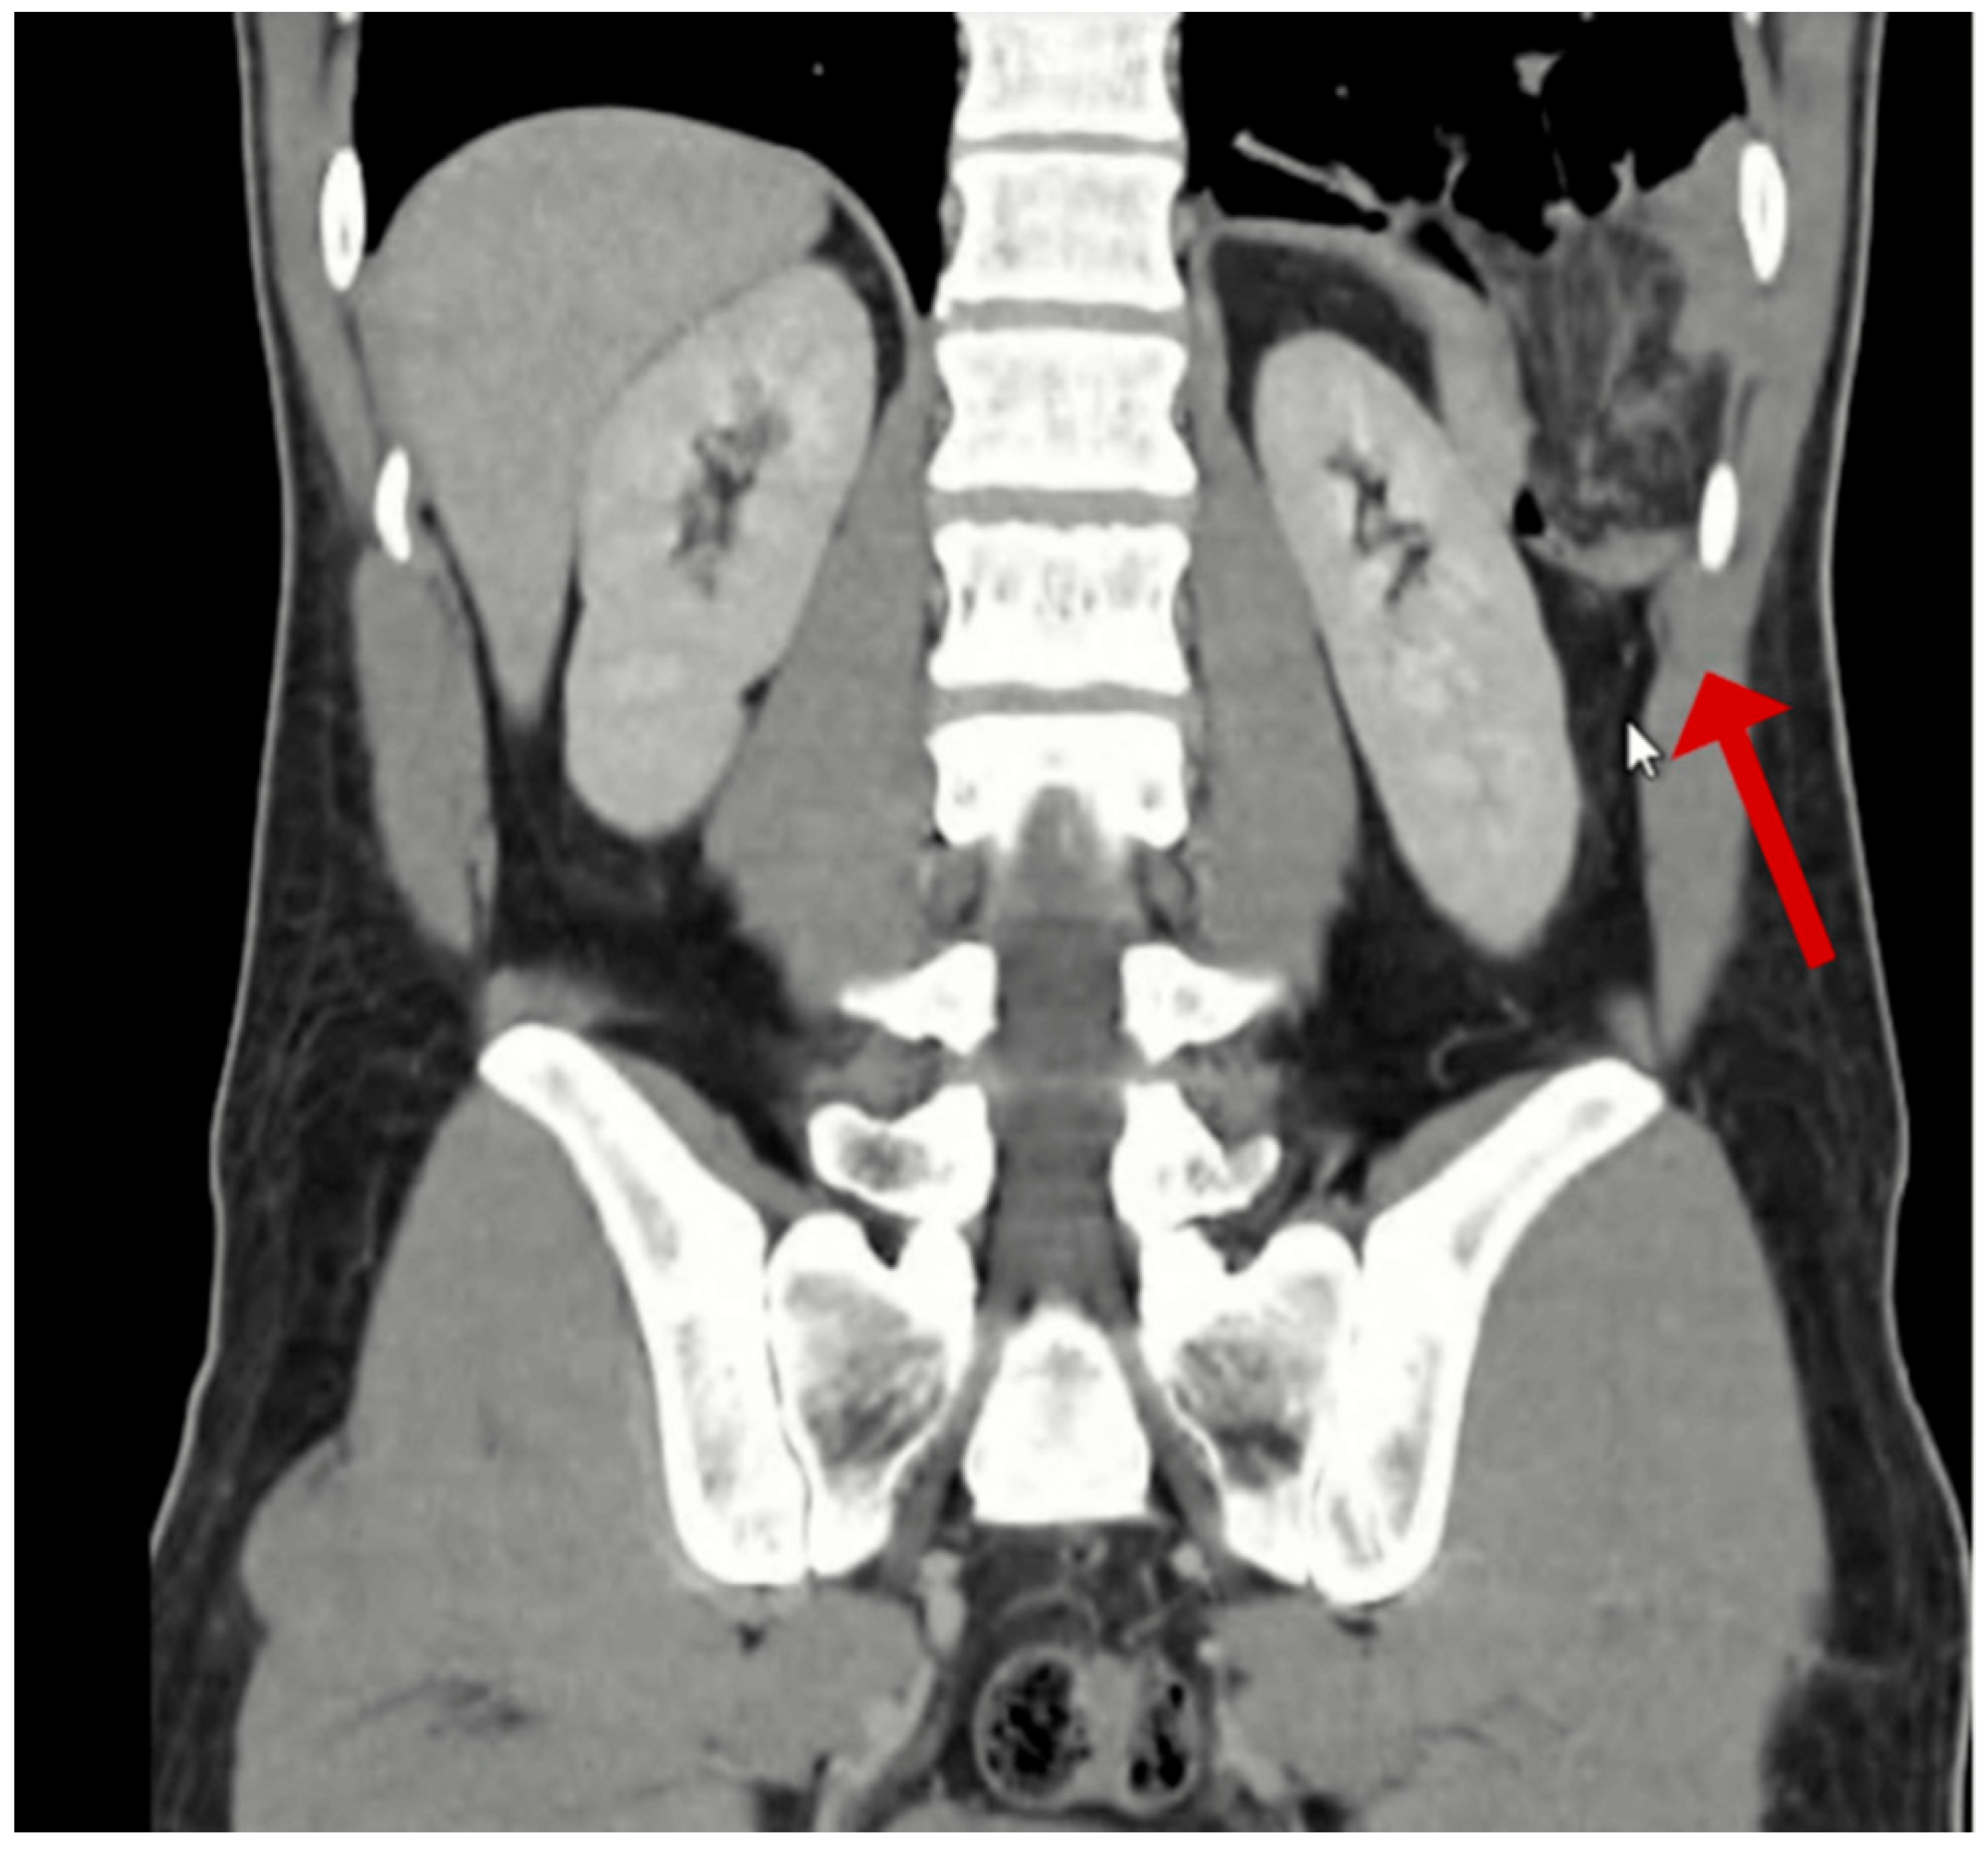

Given the initial suspicion of a perforated peptic ulcer, a non-contrast computed tomography (CT) scan was performed. This revealed a left-sided Bochdalek hernia with small bowel protrusion and signs of strangulation (Figure 1, Figure 2, Figure 3 and Figure 4).

Figure 2. Coronal view computed tomography image demonstrating diaphragmatic defect (red arrow) with herniated bowel loops visible above left hemidiaphragm.